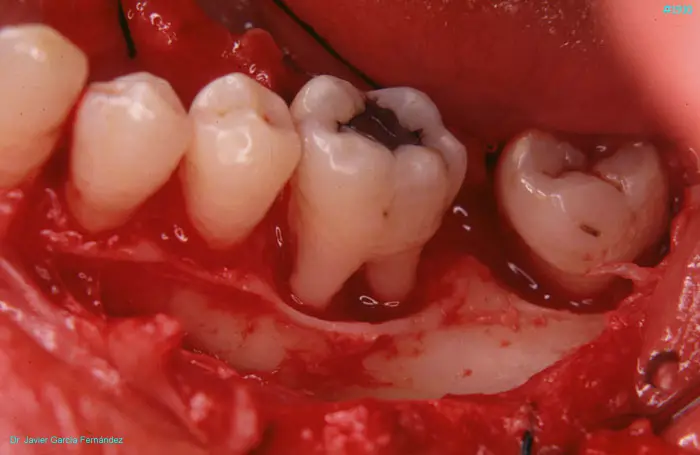

image 56